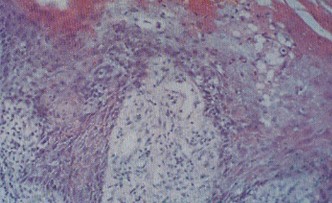

男性尖銳濕疣的發(fā)病機(jī)制發(fā)病部位肉眼可見散在疣狀或乳頭狀損害。組織病理檢查可見表皮角化不全,棘層高度肥厚,表皮突增厚延長,呈乳頭樣增生,表皮與真皮之間界限清楚。其真皮水腫,毛細(xì)血管擴(kuò)張,周圍有較致密的慢性炎癥細(xì)胞浸潤。